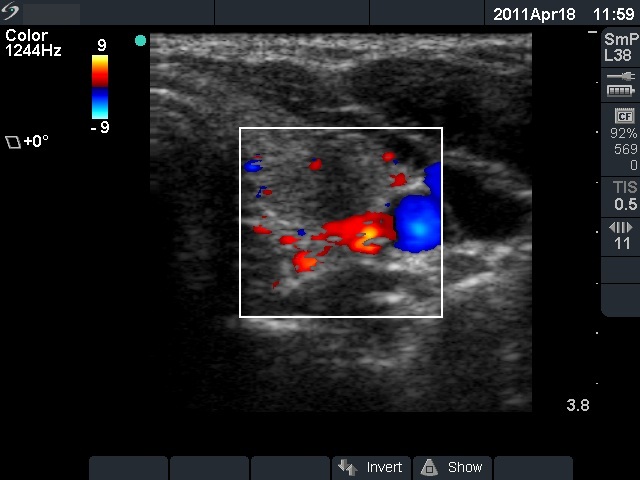

Subacute granulomatous thyroiditis - case 855

Follow-up - 5 months after initial investigation (ultrasonographic picture 6)

Left lobe, transverse scan, color Doppler mode. The lesion is almost avascular.